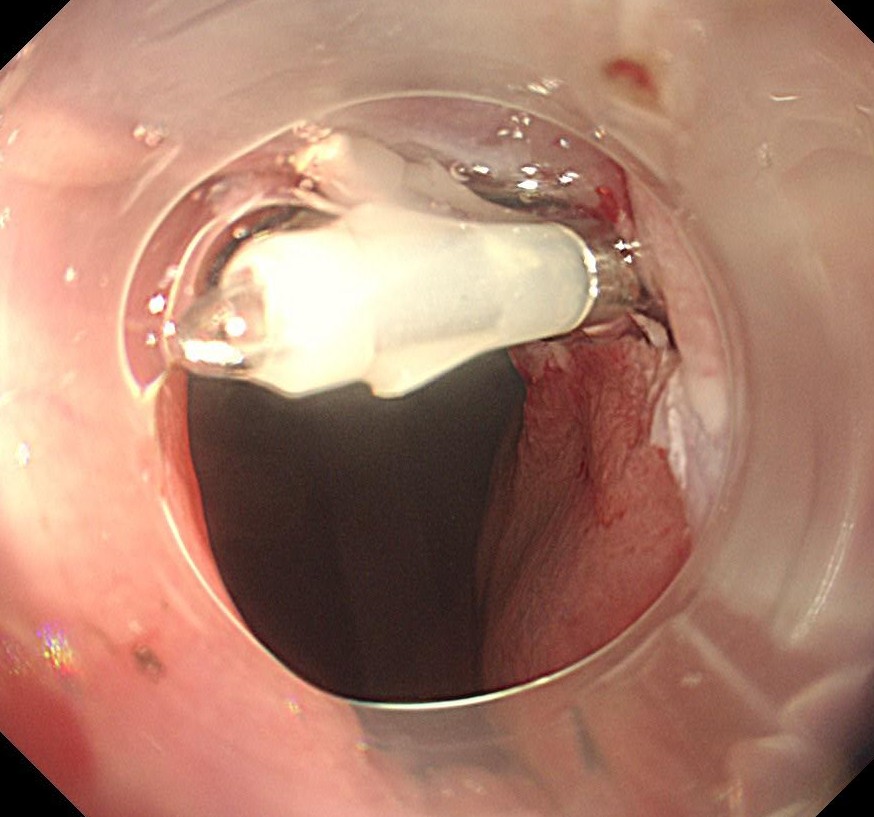

粘膜下にインジゴを含む生理食塩水を注入し、ブルーのラインで切除します(EMR)。

切除断端です。

切除断端はしっかりとクリップで閉鎖していきます。

粘膜下にインジゴを含む生理食塩水を注入し、ブルーのラインで切除します(EMR)。

切除断端です。

切除断端はしっかりとクリップで閉鎖していきます。